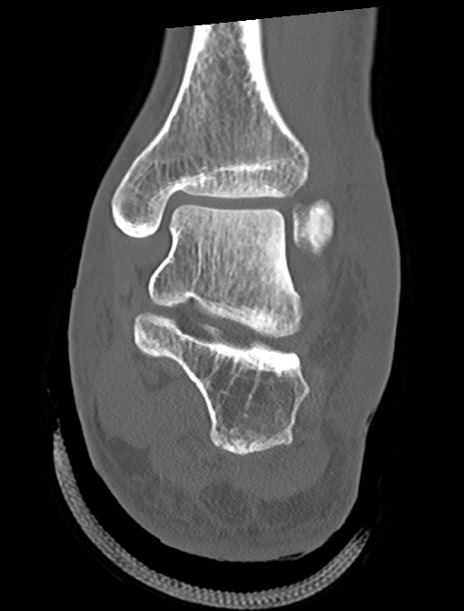

症例37 左足関節CT(冠状断像)

左足関節CT

矢状断像